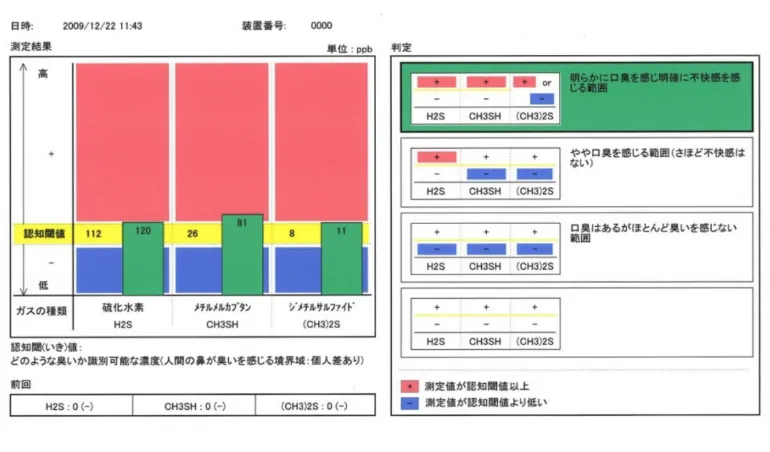

原因を特定する「ガスクロマトグラフ」

4つの検査

病気の元となる病原菌を解析できる「遺伝子検査」と、口腔の細菌数や内臓の健康状態を調べ、原因を特定する「ガスクロマトグラフ」。さらに「位相差顕微鏡検査」で歯周病になりやすい菌をチェックし、「唾液検査」で分泌物を調べ、組織や細胞をチェックします。